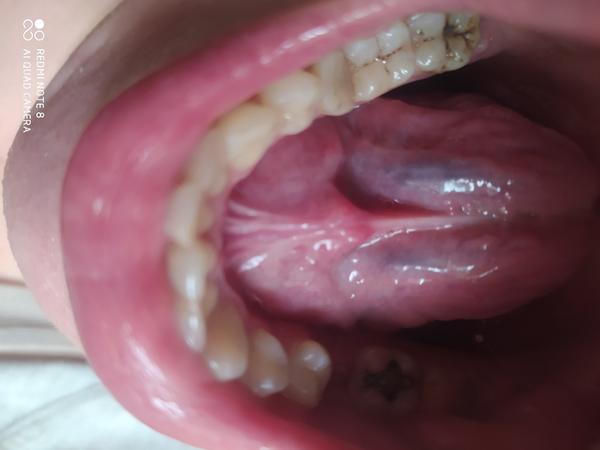

už nejakú dobu mám na jazyku takéto škvrny. Plus vzadu a na boku jazyka vzadu vyrážky. Nič ma nebolí, len sa toho neviem zbaviť. K lekárovi sa mi momentálne nedá ísť, lebo sme v karanténe.

To fialové je genciánka.

to ,čo popisujete ako vyrážky nie sú vyrážky, ale sú to tzv. papily, ktoré má každý z nás.

Škvrny na jazyku môžu byť prejavom oslabenej imunity, alebo sa objavia po nejakej prekonanej infekcii. Vhodné je užívať vitamíny skupiny B a probiotiká.